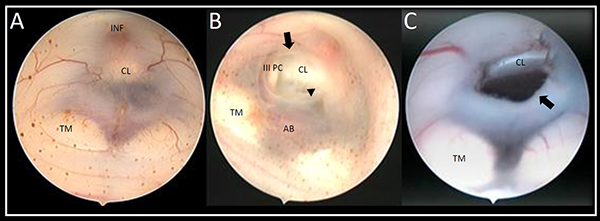

Al realizar el análisis de las grabaciones, la ostomía se consideró satisfactoria si: a) el diámetro permitió el pasaje del endoscopio, y así corroborar la correcta disección de la membrana de Liliequist, objetivando la exposición de la arteria basilar y algunas de sus ramas principales, b) visualización del movimiento ondulante de los bordes libres de la ostomía por el paso del LCR (Figura 1).

Figura 1. Imagen endoscópica obtenida desde la ostomía que permite observar la disección correcta de la membrana de Liliequist (flecha), objetivando la exposición completa de la arteria basilar y sus ramas principales. AB: arteria basilar, ACS: arteria cerebelosa superior, ACP: arteria cerebral posterior, ACPM: arteria central posteromedial izquierda CL: clivus.